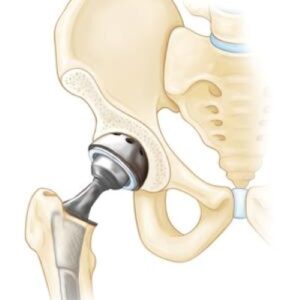

Hip Patient informationOverview Meta Description: Explore an in-depth scientific overview of Developmental Dysplasia of the Hip (DDH), its causes, risk factors, diagnosis, treatment, and long-term outcomes. SEO Keywords: developmental dysplasia of the hip, DDH, congenital hip dislocation, infant hip dysplasia, Pavlik harness, hip surgery, orthopaedics, musculoskeletal disorders Introduction Developmental Dysplasia of the